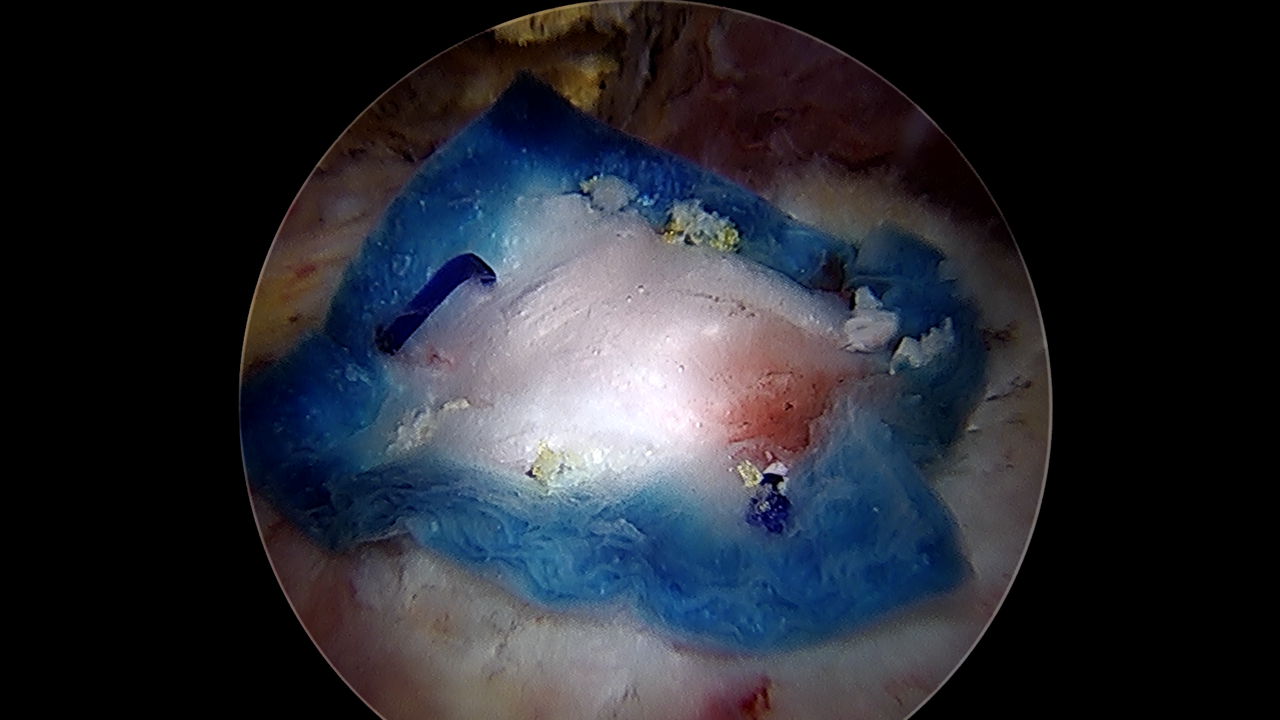

동종진피 이식술은 다른 사람의 조직에서 얻은 진피를 힘줄 위에 덮어 약해진 조직을 보강하는 치료법입니다.

이를 통해 손상된 힘줄을 보강하여 힘줄의 구조적 약점을 보완하고 조직 재생을 도와줍니다.